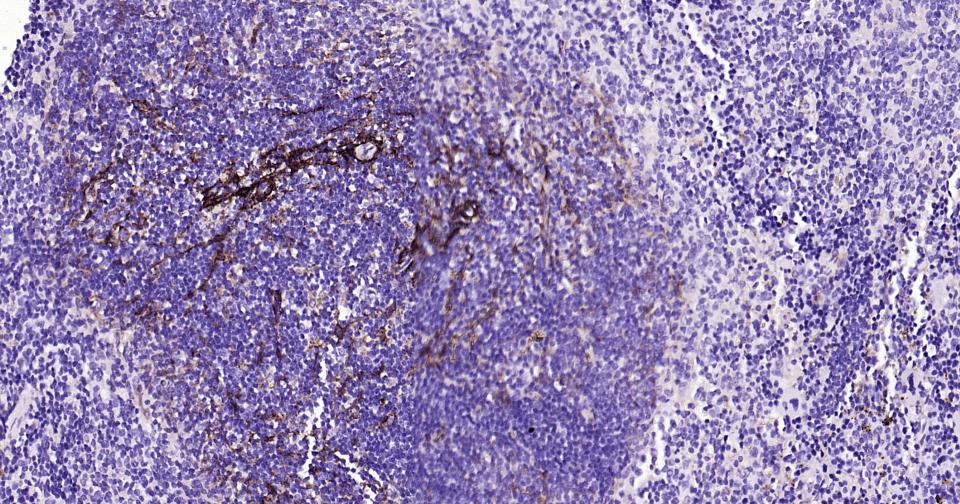

Paraformaldehyde-fixed, paraffin embedded Rat Spleen; Antigen retrieval by boiling in sodium citrate buffer (pH6.0) for 15 min; Antibody incubation with NGFR/p75NTR Monoclonal Antibody, Unconjugated(bsm-52253R) at 1:200 overnight at 4°C, followed by conjugation to the bs-0295G-HRP and DAB (C-0010) staining.